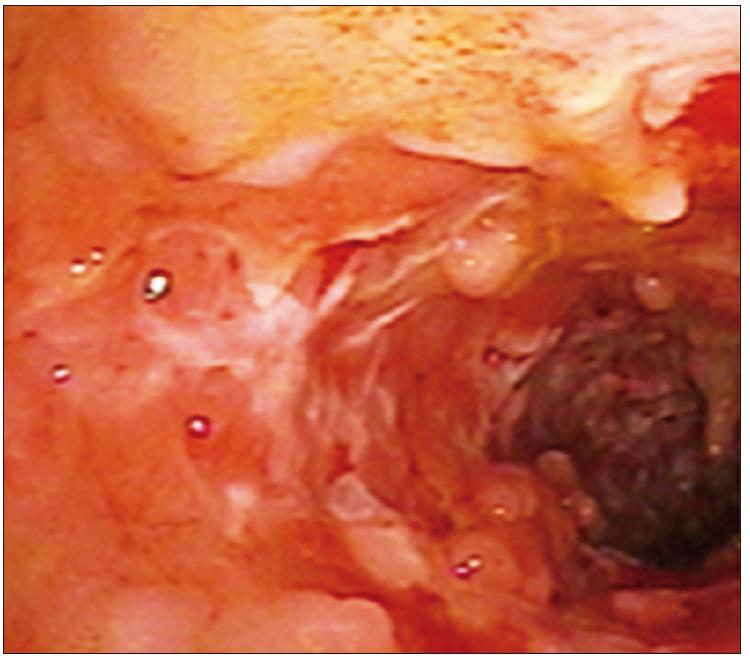

Foto 2. Colitis Ulcerosa severa con segmentos de mucosa

denudada

Reevaluar extensión y severidad: el curso remitente y recidivante de las EII obliga a la reevaluación frente a alteraciones clínicas o de los exámenes complementarios en las enfermedades ya establecidas. Durante una reactivación luminal, la visualización directa permite reevaluar el grado de actividad, obtener material indispensable para la detección de infecciones concomitantes asociadas al brote (CMV por ejemplo) o reevaluar la extensión. La utilización de los múltiples scores disponibles permite trasladar a una clasificación objetiva información sujeta a la influencia subjetiva del operador; sin embargo estas clasificaciones no reemplazan la correcta y completa descripción de los hallazgos endoscópicos. Muchos de los scores disponibles cuentan con la ventaja de ser ampliamente difundidos o sencillos, pero algunos no han recibido la validación externa necesaria. Es indispensable para el endoscopista familiarizarse con su uso.67 Al momento de la evaluación endoscópica en el contexto de un brote de EII es preciso considerar en la descripción endoscópica aquellos hallazgos relevantes o con valor pronóstico: tamaño y profundidad de las úlceras68 y progresión en la extensión del compromiso69 o la presencia de pseudopólipos, definidos como islotes de mucosa remanente entre grandes extensiones de ulceración.